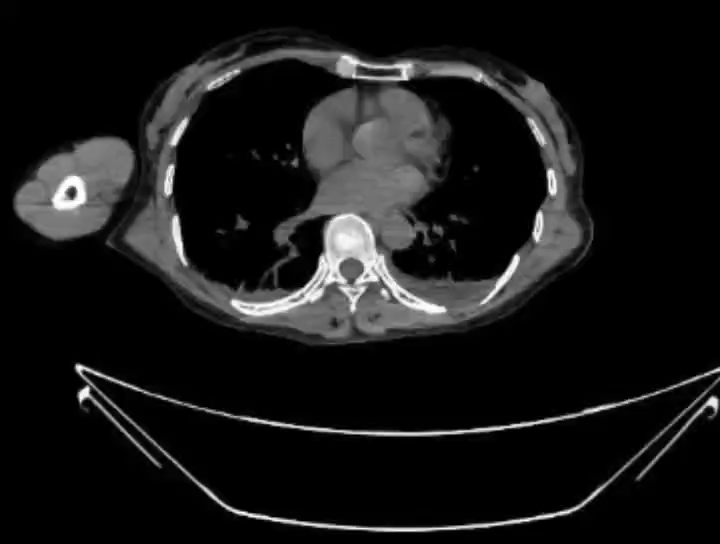

【检查】:颅脑CT平扫、胸部CT平扫、上腹部CT平扫、下腹部CT平扫、颈椎CT平扫(C4-C7椎体)、颈椎CT平扫(C1-C3椎体)提示: 1、左侧少量气胸,左肺受压约5%;双肺下叶絮状影,挫伤可能;右肺中叶、左肺上叶条索状密度增高影,纤维增殖灶?挫伤?请结合临床。2、双肺下叶结节影,Lung-RADS 2级,建议1年复查。右肺上叶钙化灶。3、左侧肩胛骨骨折;左侧第5、9、10肋骨骨折。4、左侧第4、6、8、12肋骨骨折可疑;右侧第4肋骨陈旧骨折;请结合临床。5、左肾体积稍大、密度欠均匀,肾挫伤可疑;左肾包膜下血肿;请结合临床。6、左侧肾上腺区类圆形稍高密度影,外伤性改变?其他?建议增强。7、左中腹腔、双下腹腔少许条絮状密度增高影,考虑外伤性改变,请结合临床。8、右肾多发结石(较大者约10×9mm)伴轻度积水。9、子宫稍高密度影可疑,请结合临床及超声除外病灶。10、盆腔小片状密度增高影,积血?肠管影?请结合临床及复查。11、左侧髂骨及耻骨联合、右侧骶骨翼及耻骨下支骨折。12、右侧耻骨上支、L5左侧下关节突骨折可疑,请结合临床。13、腹主动脉、髂动脉硬化。胸腰椎退变。14左髂部软组织挫伤。15、颅脑未见明显外伤性异常。16、颈椎退变伴轻度反弓。项韧带钙化。17、附见双侧下鼻甲肥大。我院急诊绿色通道 左侧肱骨正侧位片+左侧肘关节正侧位片+右侧股骨正侧位片+右侧膝关节正侧位片+云影像 提示:1、左侧肱骨中段骨折伴周围软组织稍肿胀。2、右侧膝关节、左侧肘关节、右侧股骨未见明确骨折征象。必要时 建议CT除外细微骨折。

【临床诊断】: 1、左肾挫裂伤;2.左侧创伤性气胸;3.左侧多发肋骨骨折;4.双肺挫伤;5.左侧肩胛骨骨折;6.左侧髂骨骨折;7.耻骨联合骨折;8.右侧骶骨翼骨折;9.右侧耻骨下支骨折;10. 左侧肱骨中段骨折伴周围软组织稍肿胀;11.左侧第4、6、8、12肋骨骨折?

考虑肾脏挫裂伤所致,且患者血压降低(95/58mmhg),若出血进一步加重,出现失血性休克,危及生命可能,需进一步止血治疗,因患者右肾萎缩、合并右肾结石并积水,开放手术修补困难,若修补失败需要行左肾切除术,故建议行高选择左肾动脉介入栓塞术。当日急诊介入科行超选择肾动脉栓塞术,术后血尿明显好转;经治疗后复查肾出血控制,血色素无下降。拟待患者病情好转后转入骨科进一步手术治疗。

经超滑导丝引入YASHIRO导管钩挂左侧肾动脉成功后经高压注射造影剂减影,见左肾动脉上部分支走形形态正常,未见明显造影剂滞留及外溢现象,左肾动脉下部一分支见细小分支不清,见少许造影剂外溢,逐引入微导丝、微导管(MC-PE27131)超选择该分支动脉,后手推减影见假性动脉瘤,并可见造影剂外溢,逐以350-560um明胶海绵颗粒悬液行动脉栓塞,复查造影栓塞可,退管。经超滑导丝引入YASHIRO导管钩挂右肾动脉成功后经高压注射造影剂减影,见其各个分支未见明显出血征象,未见造影剂滞留及外溢。后退管更换COBRA导管于腹主动脉成袢后引入左侧髂内动脉、臀上动脉手推减影示,各分支未见明显出血征象,未见造影剂滞留及外溢。